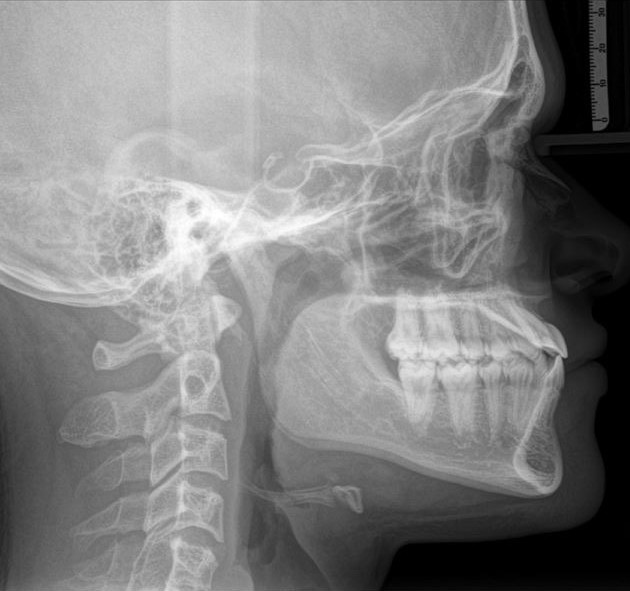

Hello my fellow niggas i know im iqcel grey etc, so thats why i need help from the higher iq blackpillers, I been debating about getting marpe + facemask(smile width), and later doing a lefort 1 + malar implants, so i need help if it would a good option to do both or just one of the options (money aint an issue) , This is my lateral RX showing a clearly class 3 only corrected teeth wise, but not in a Maxilla-Skeletal level so its basically hiding mi upper maxilla recession, I like to take this surgeries in a more conservative way to avoid getting botched, but i would like to know the opinion of more educated people in the forum, Thanks in advance.